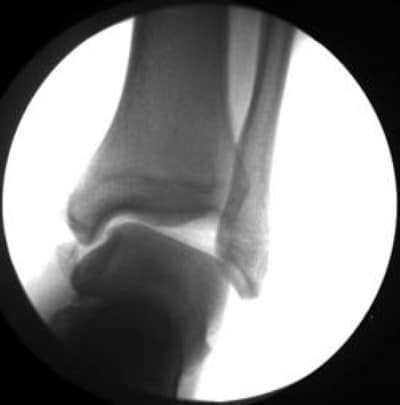

Un nouvel examen médical s’impose alors. Le professionnel de santé analysera l’articulation, vérifiera la stabilité et fera le point sur la rééducation effectuée. Si besoin, il pourra demander des examens complémentaires pour affiner le diagnostic : une IRM pour détecter d’éventuelles lésions invisibles à la radiographie, comme des fractures cartilagineuses ou des ruptures ligamentaires, voire des contusions osseuses. La radiographie de stress (ou laximétrie) permet de quantifier la laxité. L’échographie offre un aperçu précis des tendons et des ligaments. Ces examens ne sont prescrits que si le médecin les juge nécessaires au vu de l’examen clinique.